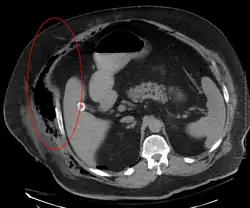

Computed tomography (CT)

If available, computed tomography (CT) is the most convenient tool in diagnosing NF due to its speed and resolution (detects about 80% of NF cases).[16] CT scan may show fascial thickening, edema, or abscess formation.[2][15] CT is able to pick up on gas within tissues better than MRI, but it is not unusual for NF to present without gas on imaging.[15] In addition, CT is helpful in evaluating complications due to NF and finding possible sources of infections.[15] Its use may be limited in pregnant patients and patients with kidney issues.[15]